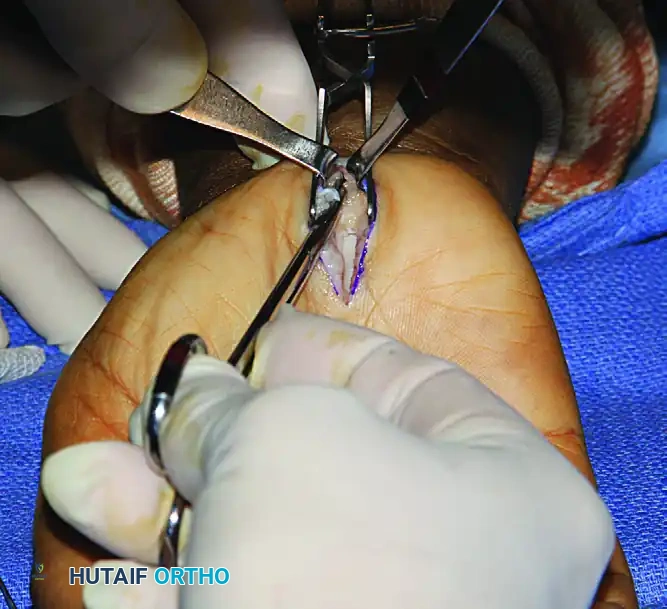

Step 3: Division of the Transverse Carpal Ligament

- Identify the proximal and distal extents of the TCL.

- Carefully divide the TCL longitudinally, staying strictly to the ulnar side of the median nerve to avoid the recurrent motor branch.

- Once the TCL is completely divided, use Metzenbaum scissors to divide the distal 2.0 cm of the antebrachial fascia proximally beneath the wrist crease.

- Verify that the distal aponeurotic fibers between the thenar and hypothenar muscles are completely released.

After the division of the TCL, the distal 2.0 cm of the antebrachial fascia is divided proximally with Metzenbaum scissors.

Step 4: Nerve Inspection and Neurolysis

- Inspect the median nerve. It should appear hyperemic (the "blush" sign) once decompressed.

- If the median nerve is found to be densely adherent to the divided radial leaf of the TCL, a careful external neurolysis may be indicated to free the nerve and prevent postoperative tethering.

In this patient, the median nerve was found adherent to the divided radial TCL leaf and subsequently required external neurolysis.